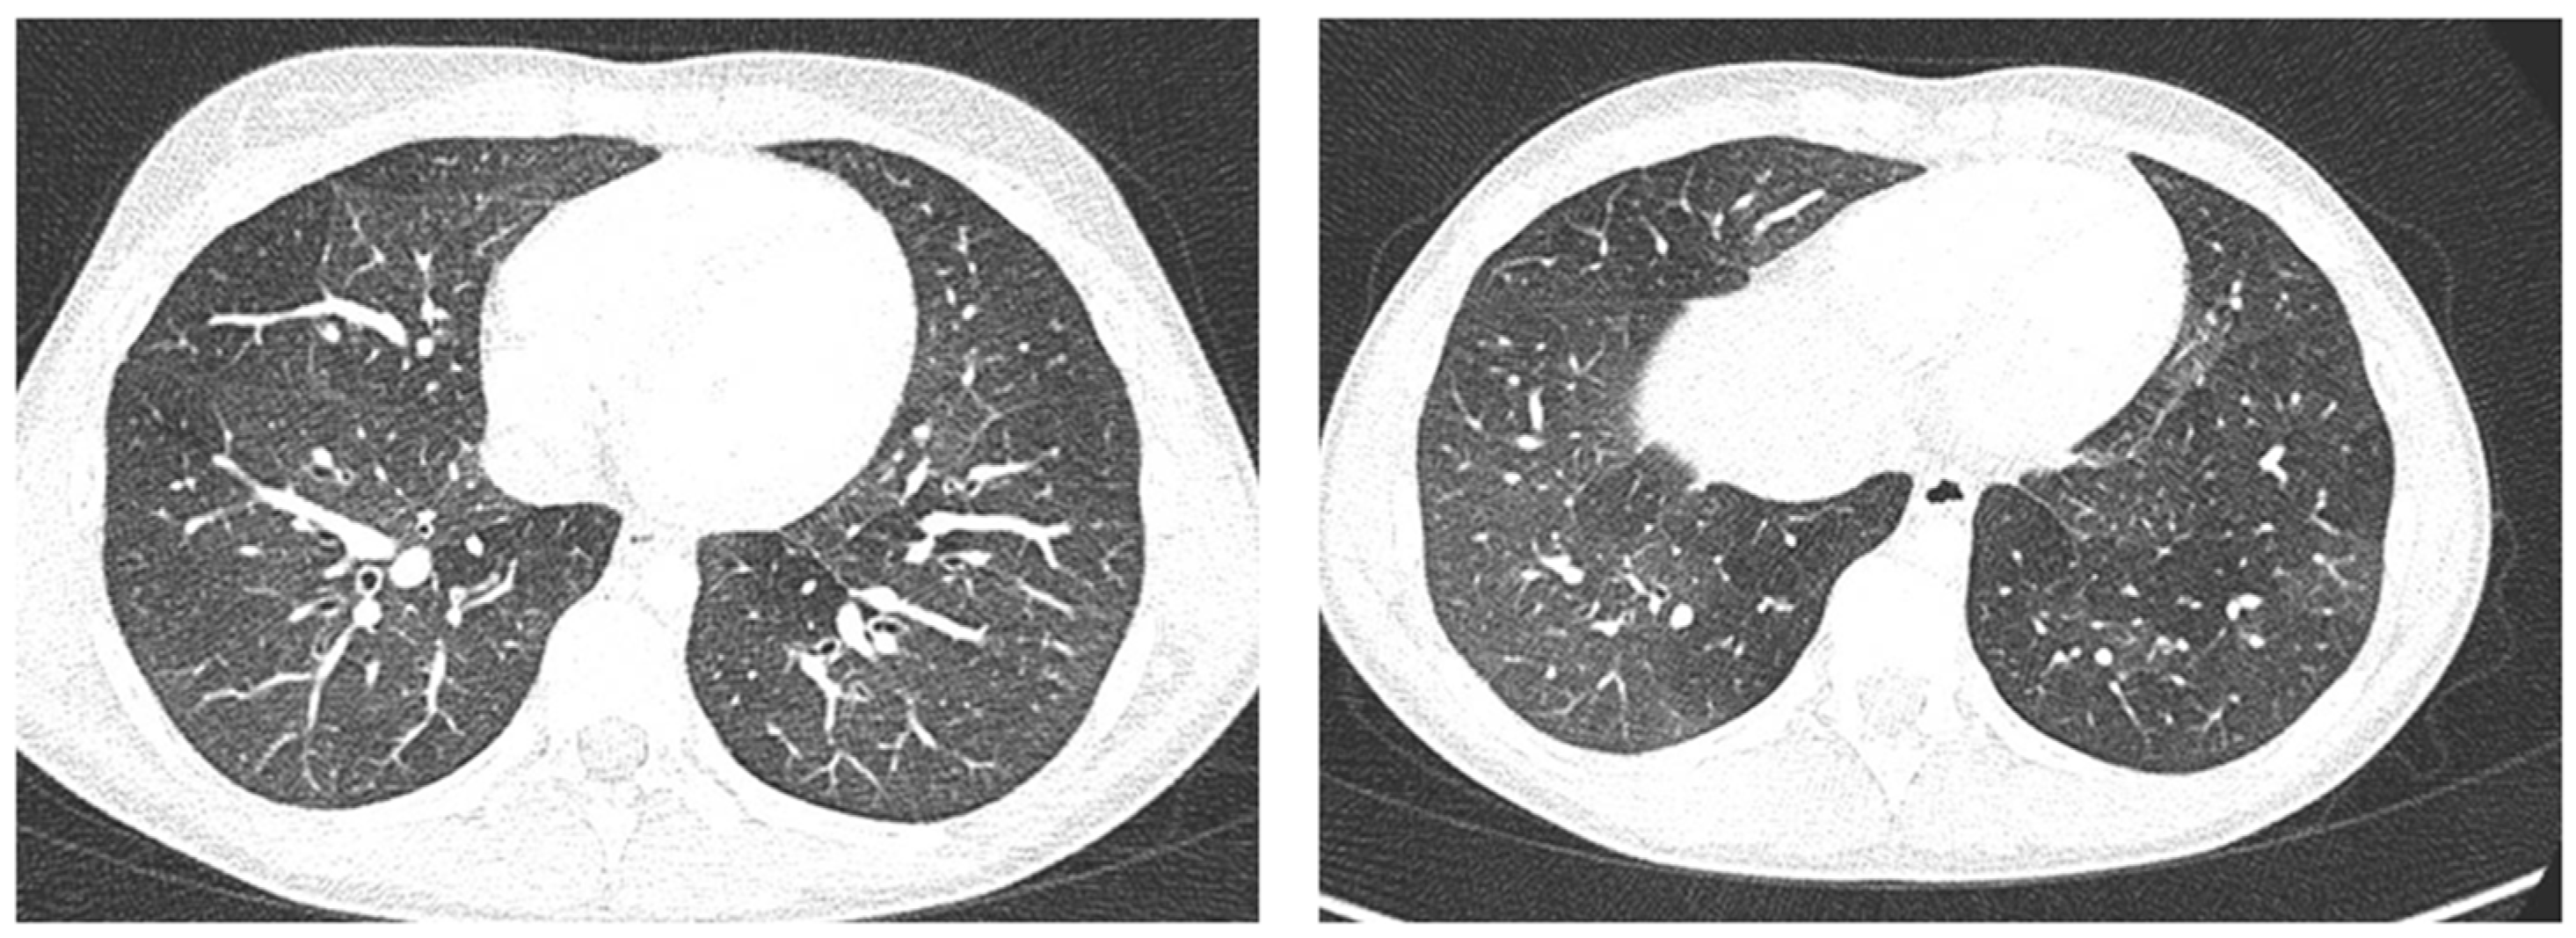

In any case, therapy for acute asthma attack and antibiotic therapy was set up, and he was admitted to the pediatric ward. Here, at the same time as the clinical evaluation, we performed LUS, which showed the presence of a diffuse SIS, and three areas of lung atelectasis, one of which—present in the left posterolateral basal area—was associated with mild reactive effusion (Figure 3). The LUS picture was highly positive, but excluded the presence of inflammatory/infectious consolidations.

Figure 3.

Grayscale lung ultrasound examination shows: an irregular pleural line in all fields explored; on the left anterior-lateral field, mainly in the apical area; (A) and on the left anterior retrocardiac field, mainly in the mid-apical area; (B) consolidations of an atelectatic nature (arrow), associated with sonographic interstitial syndrome (SIS), represented by coalescent vertical artefacts or B-lines and “white lung” areas (asterisks); (C) on the left postero-lateral field in the basal area, consolidation of about 3 cm of atelectasis nature (arrow) with static air bronchograms (punctate) (arrowheads), associated with reactive transudative pleural effusion (white asterisk); (D) on the right lateral fields, diffuse sonographic interstitial syndrome (SIS), characterized by irregularities of the pleural line (white arrowheads) and long confluent vertical artifacts (asterisks).

On the basis of these data, the antibiotic therapy was therefore suspended, oxygen therapy was set at high flows in consideration of the presence of atelectasis, and the therapy of the moderate–severe acute attack was continued with subsequent suspension of respiratory support after about a week of therapy. Adequate preventive therapy [1,2,3] was also set up. The LUS follow-up showed complete resolution of the areas of atelectasis after 4 weeks from the start of preventive therapy, whereas long vertical artifacts and irregularities of the pleural line were still present.

In our cases (Table 1), particularly in the first three cases—children with asthma not controlled due to an inadequate preventive therapy for age, phenotype, and severity of the clinical picture [1,2]—LUS was highly positive (Figure 1, Figure 3 and Figure 5). It showed the presence of lung atelectasis, which resolved slowly after weeks of therapy of the acute attack and the beginning of adequate preventive therapy. On the contrary, in case 4 and 5—children with asthma well controlled by adequate preventive therapy—LUS was not highly positive (Figure 6 and Figure 7). In fact, it did not show large atelectasis, but a slight SIS in case 4, and a SIS suggestive of viral infection of the small airways in case 5 [14,15].